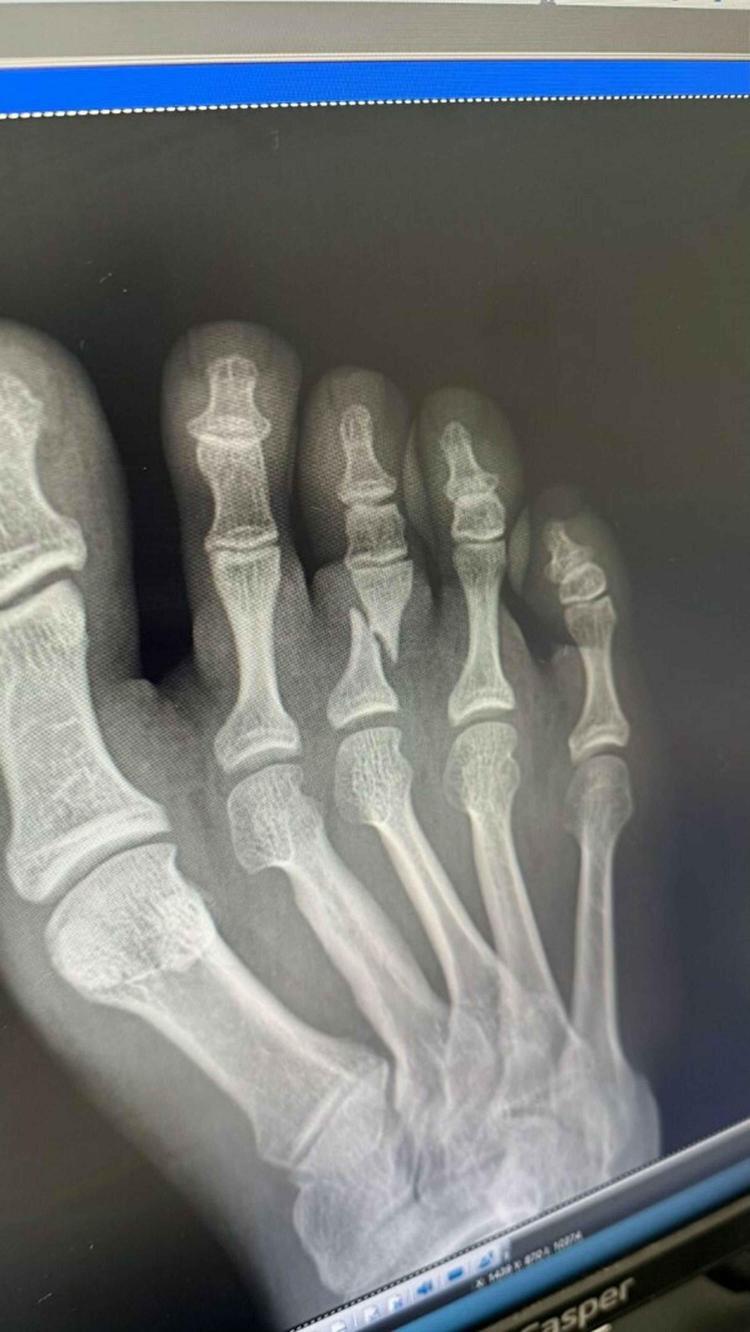

İzmir'in Buca ilçesinde yaşayan ve spora 14 yaşındayken bireysel fitness yaparak başlayan, lise mezunu Emin Özer, Kick Boks branşında yaklaşık 4 yıldır çift antrenman yaparak hazırlandığı Çin'de 07-17 Ağustos tarihleri arasında düzenlene 2025 Dünya Oyunları'ndan gümüş madalya ile döndü. Final maçının 30'uncu saniyesinde sağ ayağındaki üçüncü parmağı kırılan Özer, maçı bırakmayarak mücadelesine devam etti.

Çin'deki Dünya Oyunları için sıkı bir hazırlık süreci geçirdiğini kaydeden Emin Özer, dünya şampiyonu olmayı hedeflediğini belirtip şöyle devam etti: "Yaklaşık 4 senedir sabah akşam demeden antrenman yapıyorum. Her şeyden fedakarlık yapıyorum. Çünkü çok büyük bir organizasyon, bir bakıma olimpiyatın bir alt kademesi. Tüm devletler birinci olmayı amaçlıyor. Türk bayrağını en iyi şekilde temsil etmek için federasyonun desteği ile oraya gittik. 3 maç yaptım. Geçmiş dünya ve Avrupa şampiyonu olan Polonyalı ve Özbek rakibimi yendim. Finalde Ukraynalı rakibim ile maç yaptım. İlk 30 saniyede attığım bir tekme sonucu ayak parmağım kırıldı. Devam ettim ama istediğim şekilde kendimi veremedim.

Güç aldığım sağ ayak olduğu için üzerine basamıyordum. Mücadele ettik, sonuna kadar savaştık ama kırık ayakla buraya kadar oldu. Kaybettim maçı ve ikinci oldum. Birinciliği hedefliyordum ikinci olarak o kürsüde olmak Türk bayrağını göstermek yine de gurur vericiydi. Ama isteriz ki devletimiz bizi biraz daha fazla desteklesin. Bundan sonra daha büyük oynayıp daha çok şampiyon olmak istiyorum. 3 ay sonra dünya şampiyonası var inşallah orada şampiyon olacağım. Daha 21 yaşındayım ve önümde yürüyecek daha uzun yol var."

Biz sporcumuza 'Çekilmek istiyorsan çekilebilirsin' dedik. Ayağının kırık olduğunu görüyorduk. Anında şişti ayağı. 'Hocam devam etmek, bayrağımızı en iyi şekilde temsil etmek istiyorum' dedi. Biz de kararına saygı duyup engellemedik. Ama ayağındaki kırık daha da büyüdü. Şimdi Birleşik Arap Emirlikleri'nin başkenti Abu Dabi'de düzenlenecek olan Kick Boks Dünya Şampiyonası'na hazırlanıyoruz. İnşallah hızlı bir şekilde yetiştireceğiz onu" ifadelerini kullandı.